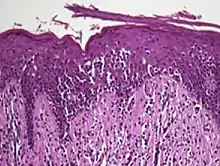

Histology

The criteria for the disease are established on the skin biopsy by the presence of the following:[18]

- Presence of cancer cells with twisted contours (cerebriform nuclei)

- In the patch and plaque stages, the cancer cells are seen in the epidermis (the most superficial layer of skin).[19] This is referred to as epidermotropism.

- Pautrier's microabcesses, aggregates of four or more atypical lymphocytes arranged in the epidermis. Pautrier microabcesses are characteristic of mycosis fungoides but are generally absent.

- In the tumour stage, the cancer cells move into the dermis (the deeper layer of skin)[19]

- Large cell transformation, where clonally identical lymphocytes in the lesion exhibit hypertrophy. In transformed cells, presence of the CD30 receptor is associated with improved survival[20]

Traditionally, mycosis fungoides has been divided into three stages: premycotic, mycotic and tumorous. The premycotic stage clinically presents as an erythematous (red), itchy, scaly lesion. Microscopic appearance is non-diagnostic and represented by chronic nonspecific dermatosis associated with psoriasiform changes in epidermis.

In the mycotic stage, infiltrative plaques appear and biopsy shows a polymorphous inflammatory infiltrate in the dermis that contains small numbers of frankly atypical lymphoid cells. These cells may line up individually along the epidermal basal layer. The latter finding if unaccompanied by spongiosis is highly suggestive of mycosis fungoides. In the tumorous stage a dense infiltrate of medium-sized lymphocytes with cerebriform nuclei expands the dermis.